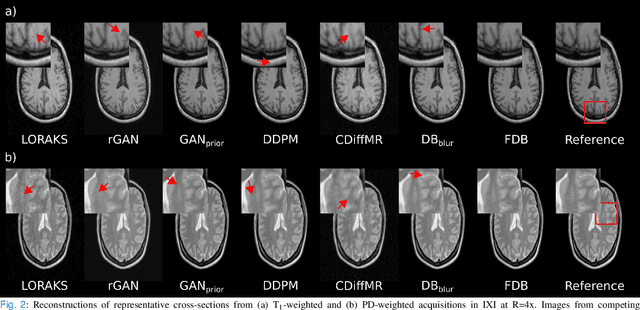

Abstract:Recent years have witnessed a surge in deep generative models for accelerated MRI reconstruction. Diffusion priors in particular have gained traction with their superior representational fidelity and diversity. Instead of the target transformation from undersampled to fully-sampled data, common diffusion priors are trained to learn a multi-step transformation from Gaussian noise onto fully-sampled data. During inference, data-fidelity projections are injected in between reverse diffusion steps to reach a compromise solution within the span of both the diffusion prior and the imaging operator. Unfortunately, suboptimal solutions can arise as the normality assumption of the diffusion prior causes divergence between learned and target transformations. To address this limitation, here we introduce the first diffusion bridge for accelerated MRI reconstruction. The proposed Fourier-constrained diffusion bridge (FDB) leverages a generalized process to transform between undersampled and fully-sampled data via random noise addition and random frequency removal as degradation operators. Unlike common diffusion priors that use an asymptotic endpoint based on Gaussian noise, FDB captures a transformation between finite endpoints where the initial endpoint is based on moderate degradation of fully-sampled data. Demonstrations on brain MRI indicate that FDB outperforms state-of-the-art reconstruction methods including conventional diffusion priors.